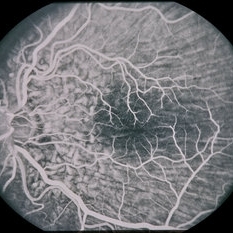

45-year-old Hispanic male with hypotony from over-filtration.